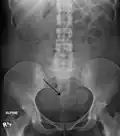

Diagnosis

Physical examination and ultrasound are sufficient for diagnosing uterine fibroids in the majority of people. When ultrasound findings are inconclusive, magnetic resonance imaging (MRI) may be able to confirm the diagnosis of uterine fibroids in most cases. In addition, MRI can identify benign uterine fibroids with atypical imaging features and fibroids with variant growth patterns. MRI can also identify other uterine (e.g. adenomyosis, endometrial polyps, endometrial cancer) and extrauterine (e.g. benign and malignant ovarian tumors, endometriosis) disorders that may mimic the appearance of uterine fibroids and/or contribute to the patient's symptoms.[38] However, a small proportion of uterine fibroids can mimic other malignant uterine tumors (e.g. leiomyosarcoma) on all available imaging modalities (e.g. ultrasound, CT, MRI and PET-CT).[38]